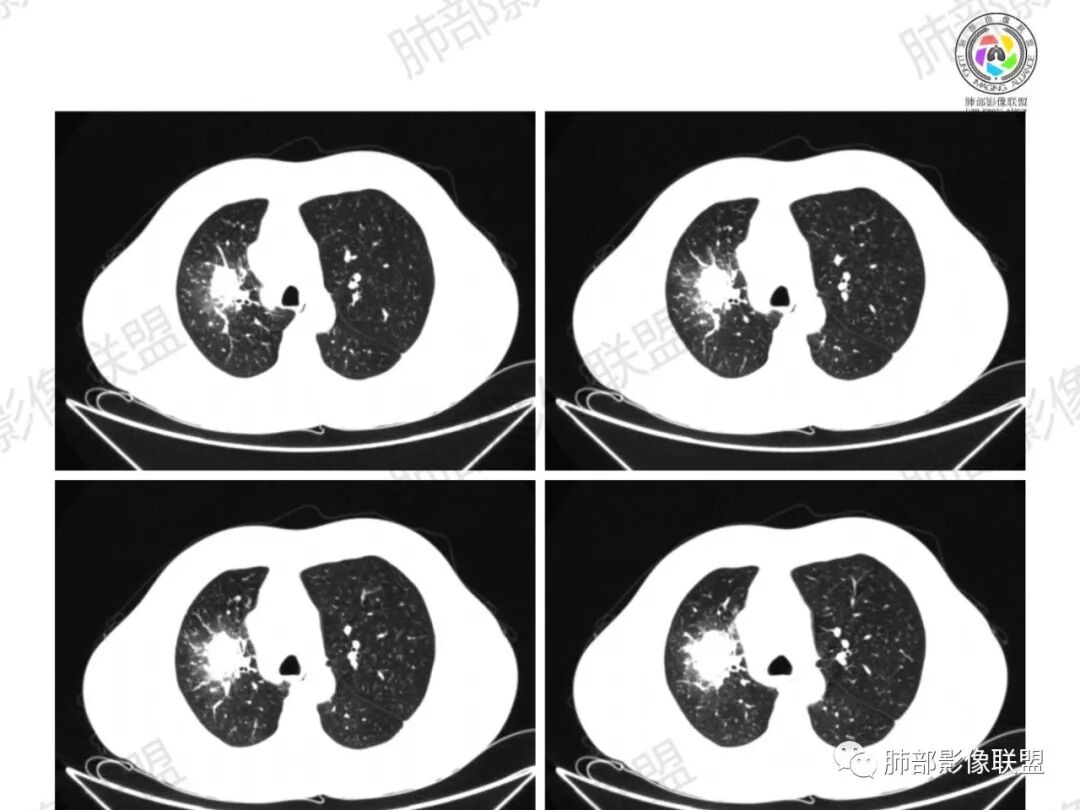

右上叶肺门区肿块,较大:

前段支气管鼠尾状狭窄,壁增厚

尖段/后段支气管受压推移

浅分叶,内部坏死部分边界不清,实性部分明显强化

远端有些花花草草

总觉得有部分指套改变

多发树芽,病灶边缘模糊的GGO

怎么看怎么不符合恶性,远端并不是明显的阻塞性炎改变,一是主要表现为树芽和结节,二是未按责任支气管分布。

1、坏死区内寸草不生;2、病灶环形强化;3、远端树芽和结节;4、远端不是阻塞性炎症,而是树芽和结节,右肺上叶前后段都有,后段为主,而堵塞的支气管应该是前段;这些树芽的位置不是堵塞支气管的责任区;5、支气管不是突然截断堵塞,而是逐渐狭窄;6、纵隔淋巴结是椭圆形增大,内有坏死,不是肿瘤的圆形饱满;7、支气管周围粘液样坏死,符合仙人掌结核改变;

3、阻塞性炎症:这个病例远端的散在病灶分布与责任支气管不符,所以不是阻塞性炎症,应该是树芽;